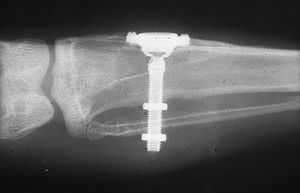

While studying bone cells in a rabbit femur using a titanium chamber, Branemark was unable to remove it from bone. His realization that bone would adhere to titanium led to the concept of osseointegration and the development of modern dental implants. The original xray of the chamber embedded in the rabbit femur is shown (made available by Branemark).

In the 1950s research was being conducted at Cambridge University in England to study blood flow in vivo. These workers devised a method of constructing a chamber of titanium which was then embedded into the soft tissue of the ears of rabbits. In 1952 the Swedish orthopaedic surgeon, Per-Ingvar Brånemark, was interested in studying bone healing and regeneration. During his research time at Lund University he adopted the Cambridge designed "rabbit ear chamber" for use in the rabbit femur. Following the study, he attempted to retrieve these expensive chambers from the rabbits and found that he was unable to remove them. Brånemark observed that bone had grown into such close proximity with the titanium that it effectively adhered to the metal. Brånemark carried out further studies into this phenomenon, using both animal and human subjects, which all confirmed this unique property of titanium.

Although Brånemark had originally considered that the first work should centre on knee and hip surgery, he finally decided that the mouth was more accessible for continued clinical observations and the high rate of edentulism in the general population offered more subjects for widespread study. He termed the clinically observed adherence of bone with titanium as "osseointegration". In 1965 Brånemark, who was by then the Professor of Anatomy at Gothenburg University in Sweden, placed his first titanium dental implant into a human volunteer.[5](p. 626)